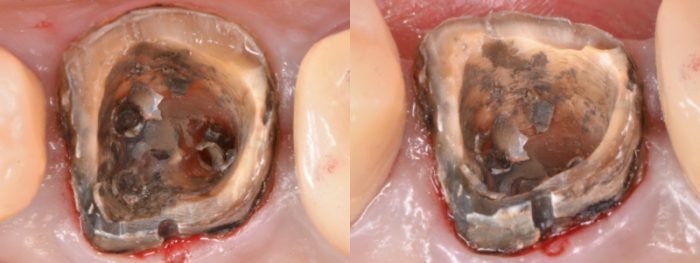

被せ物を外すと、

金属製の土台が入っています。それも外します。

歯の中は茶色のものがたくさん。

全て長い年月をかけて細菌が増殖したものです。

外した金属や接着剤も、細菌に汚染されています。

通常は被せ物や土台を外す前、初めにラバーダムを設置します。

今回は残っている歯の量が少ない可能性が高かったため、ラバーダムを安定して固定するための方法を決める目的で、この段階でラバーダムを設置しました。